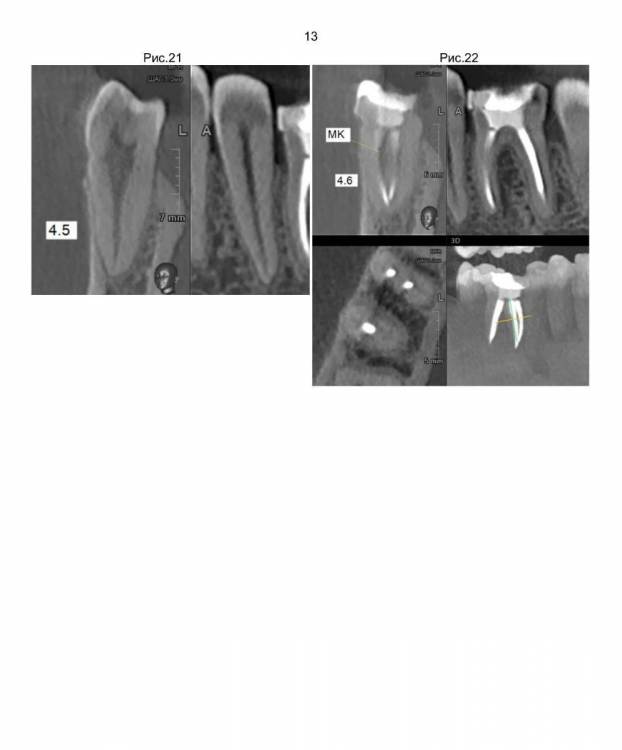

По второму плану лечения зубы 2.6 и 4.6 стачиваются, устанавливаются корневые вкладки и ставятся коронки.